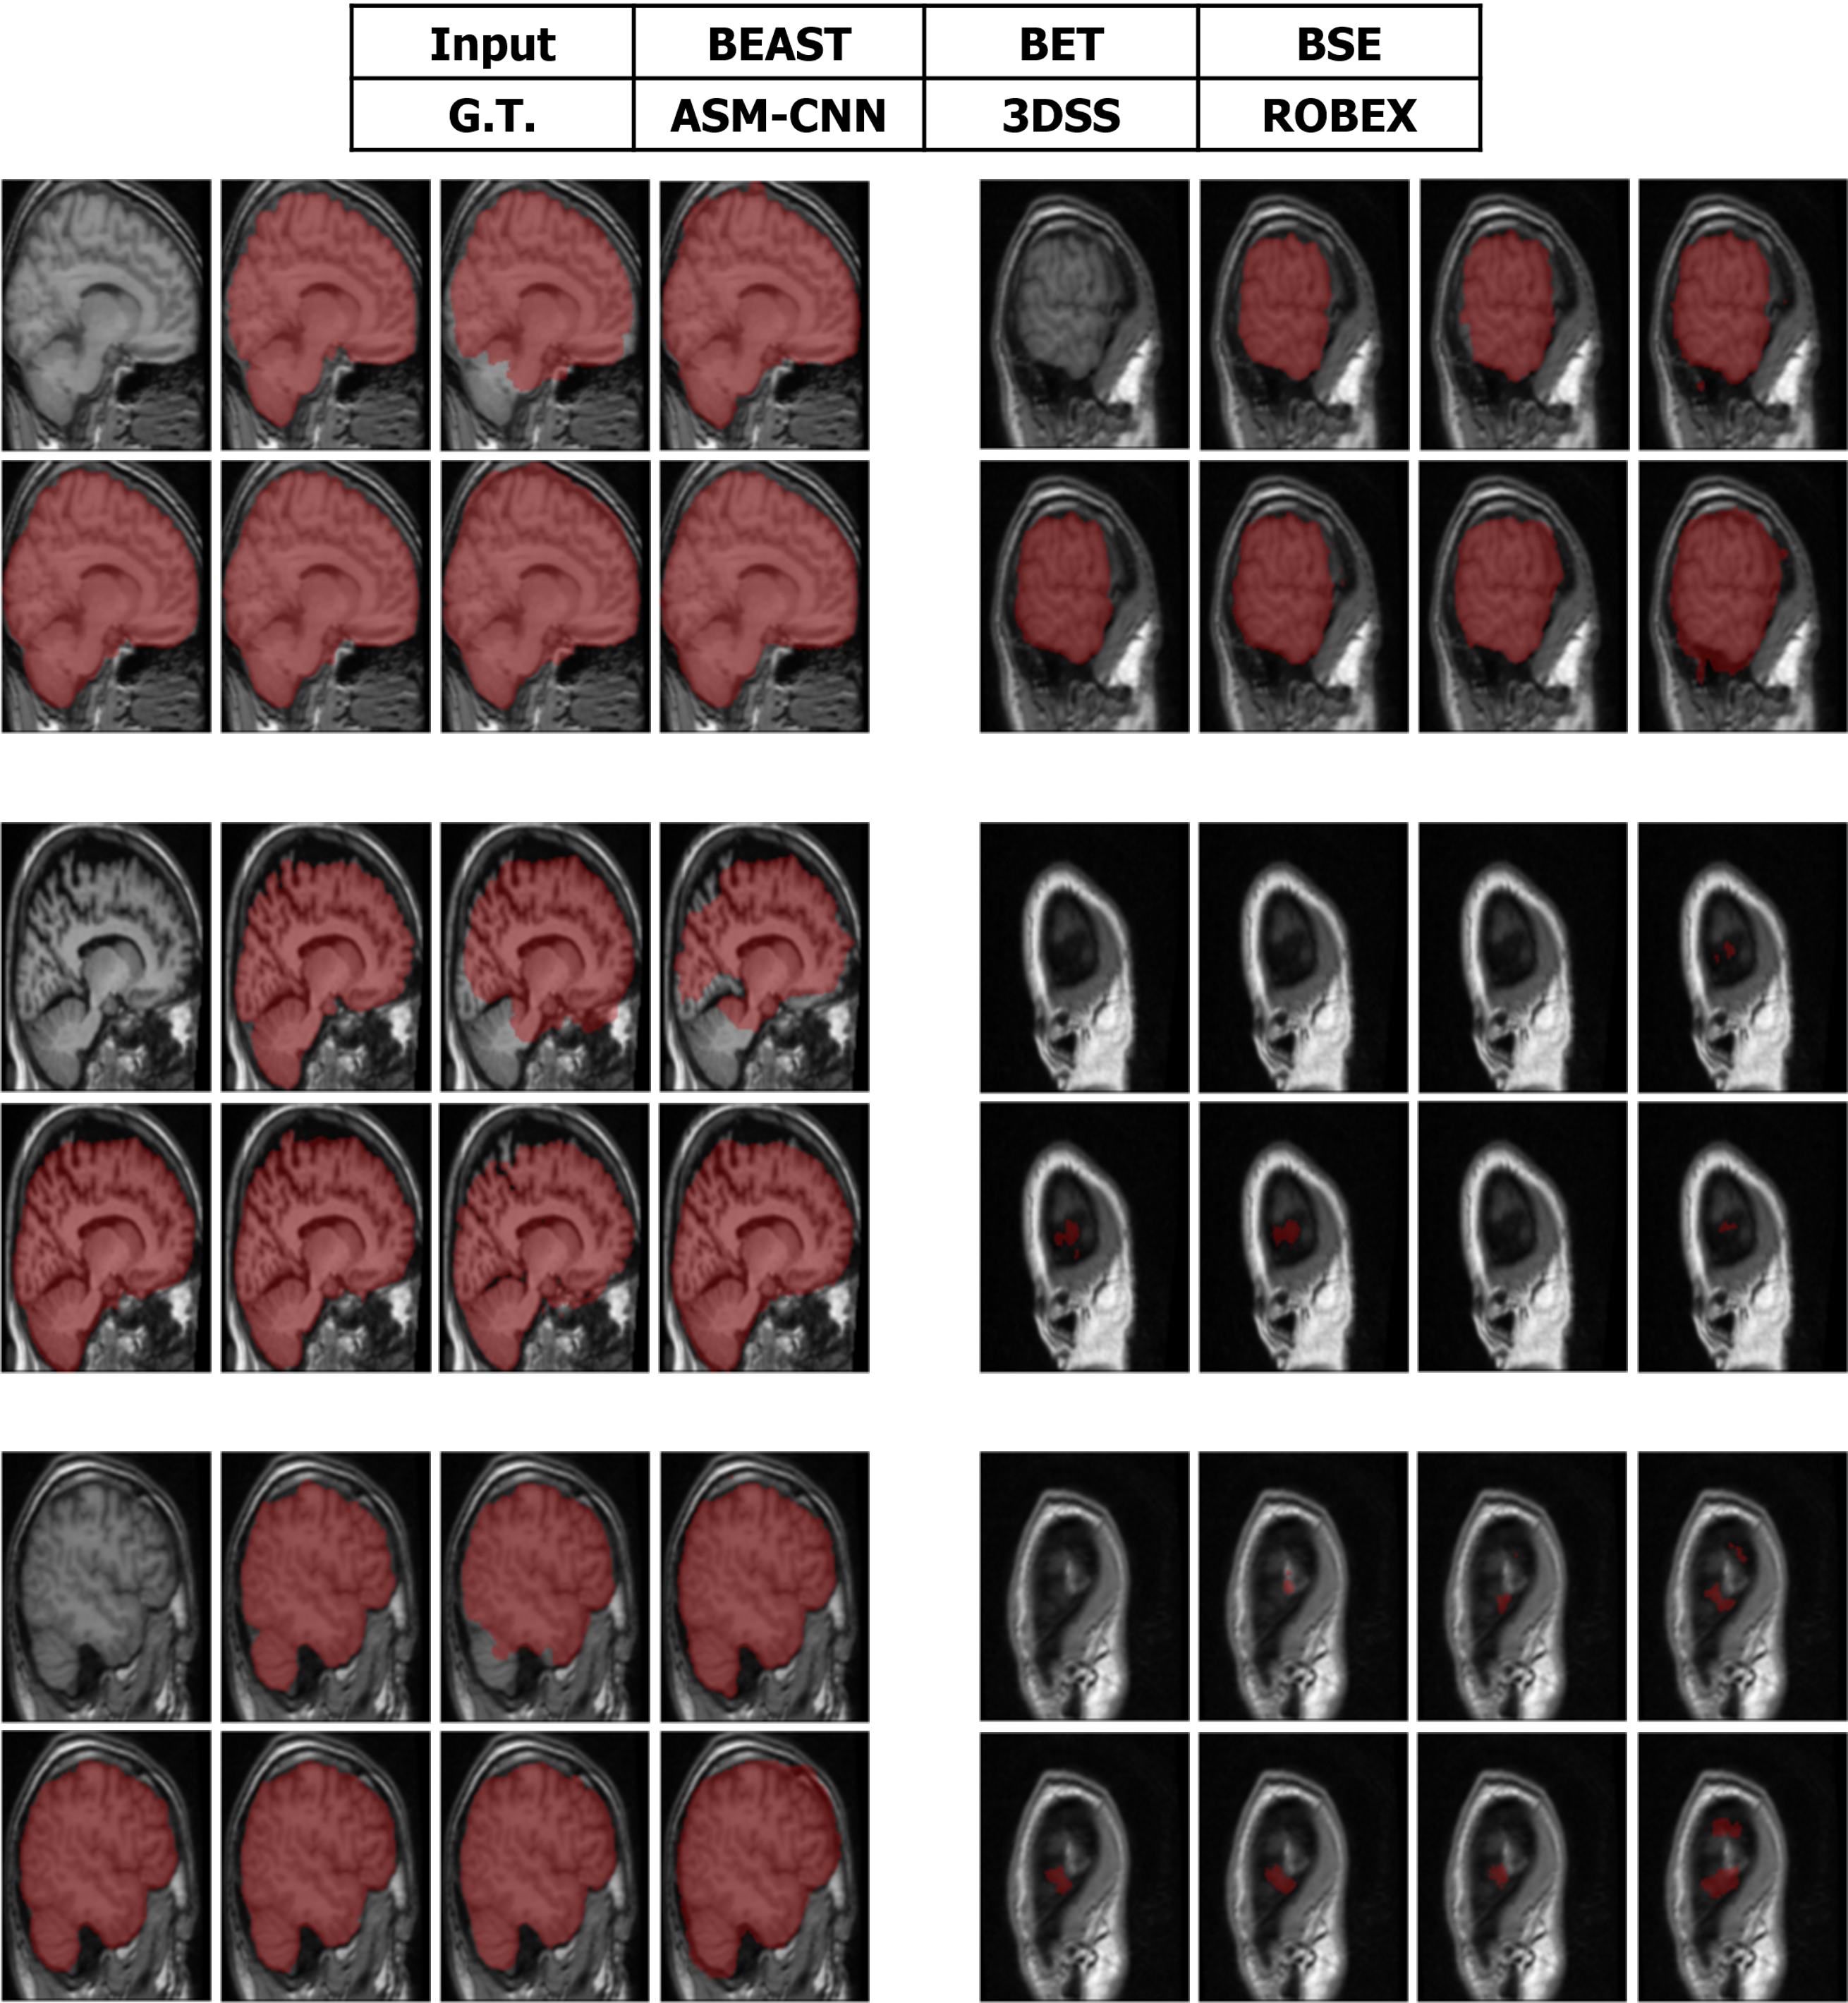

Refer to caption

Figure 11: The comparison between ASMCNN with other methods on IBSR dataset.

Segmentation results of ASMCNN and seven other methods in the sagittal plane for the three datasets are illustrated in Figures 11, 12 and 13 respectively. Each figure includes six typical testing scans from all three groups (two scans for each group). Although ASMCNN works with the sagittal plane, it also produces correct segmentation in two other planes. Figure 14 shows the comparison between our approach and other methods on each dataset for these two planes.

Figure 12: The comparison between ASMCNN with other methods on OASIS dataset.

Figure 13: The comparison between ASMCNN with other methods on LPBA dataset.

ASMCNN can provide extremely accurate segmentation in these three datasets. We achieve the same results as ROBEX with smooth boundaries and keep both gray and dura matter inside extracted brains for most cases, which are usually left out by ROBEX. Although there are minor leakages into the skull by ASMCNN, its occurrence is less than both ROBEX and BEAST, as it only generates a smaller number of over-segmentation results. The critical impact of the method is that it can precisely work for small-size brains in Group I as well, meanwhile other techniques usually fail. As shown in Figures 11 - 13, our results are mostly similar to the ground-truth images especially for tiny-size brains (Figure 11). The method does not avoid a few false negatives and false positives in this group on account of the complexity of the brain structure. Nevertheless, ASMCNN can mostly obtain a better performance than others with higher accuracy.